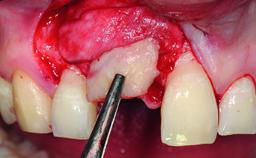

Replacement of a Failing Upper Right Central Incisor, Ridge Preservation and Late Placement of a NC Bone Level Implant

A 30-year-old patient presented at our clinic with a chief complaint of pain in her endodontically treated right maxillary central incisor (tooth 11) with a post-and-core and a fixed single crown. She had a very high lip line, a medium to thin soft-tissue phenotype, and a medium scalloped gingival contour. She also had high esthetic expectations because of her young age and beautiful smile. However, her expectations were realistic and she understood the risks of the treatment. At the initial clinical examination there was a slight mobility of tooth 11; no fistula was observed. The patient also had a single crown on the adjacent tooth 21. Both restorations were old and esthetically deficient. A digital periapical radiograph showed a very small periapical radiolucency, a thick intraradicular post, and no separation between root fragments.

Bone Augmentation Staged

Augmentation Materials Xenogenous|Membrane

Soft Tissue Grafting Simultaneous